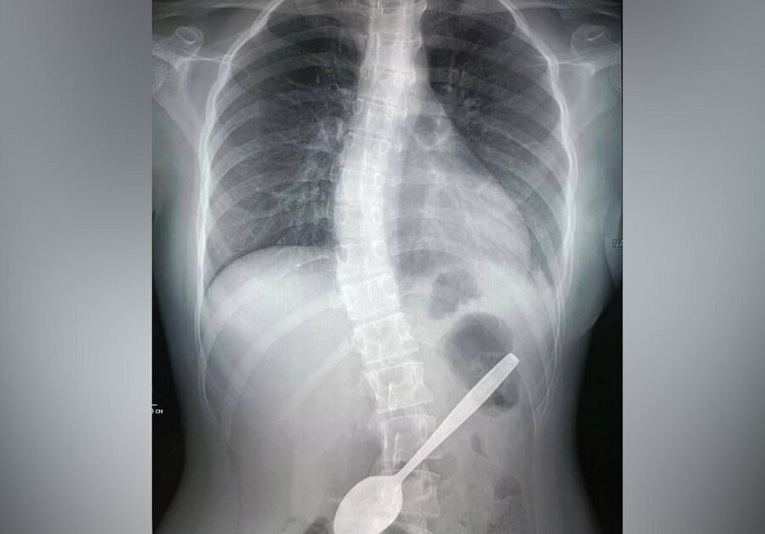

В Детский клинический центр имени Рошаля поступила девочка, которая случайно проглотила ложку. Врачи провели ей рентгенографию органов брюшной полости и подтвердили наличие инородного тела в желудке. Школьницу госпитализировали в хирургическое отделение.

Врач-эндоскопист Дарья Степаненко рассказала, что во время операции они осмотрели пищевод и желудок пациентки с помощью видеоскопа. Выяснилось, что ложка тонкой частью упиралась в стенку желудка, а широкой частью уходила в луковицу двенадцатиперстной кишки.

«Эндоскопической петлёй мы извлекли ложку из луковицы двенадцатиперстной кишки, а после эндоскопическими щипцами по типу «крысиный зуб» протянули её до глотки. После этого хирургическим зажимом мы полностью извлекли инородное тело из организма девочки», – сообщила Степаненко. По её словам, операция длилась около часа и прошла успешно. Девочка чувствует себя хорошо и уже выписана домой.